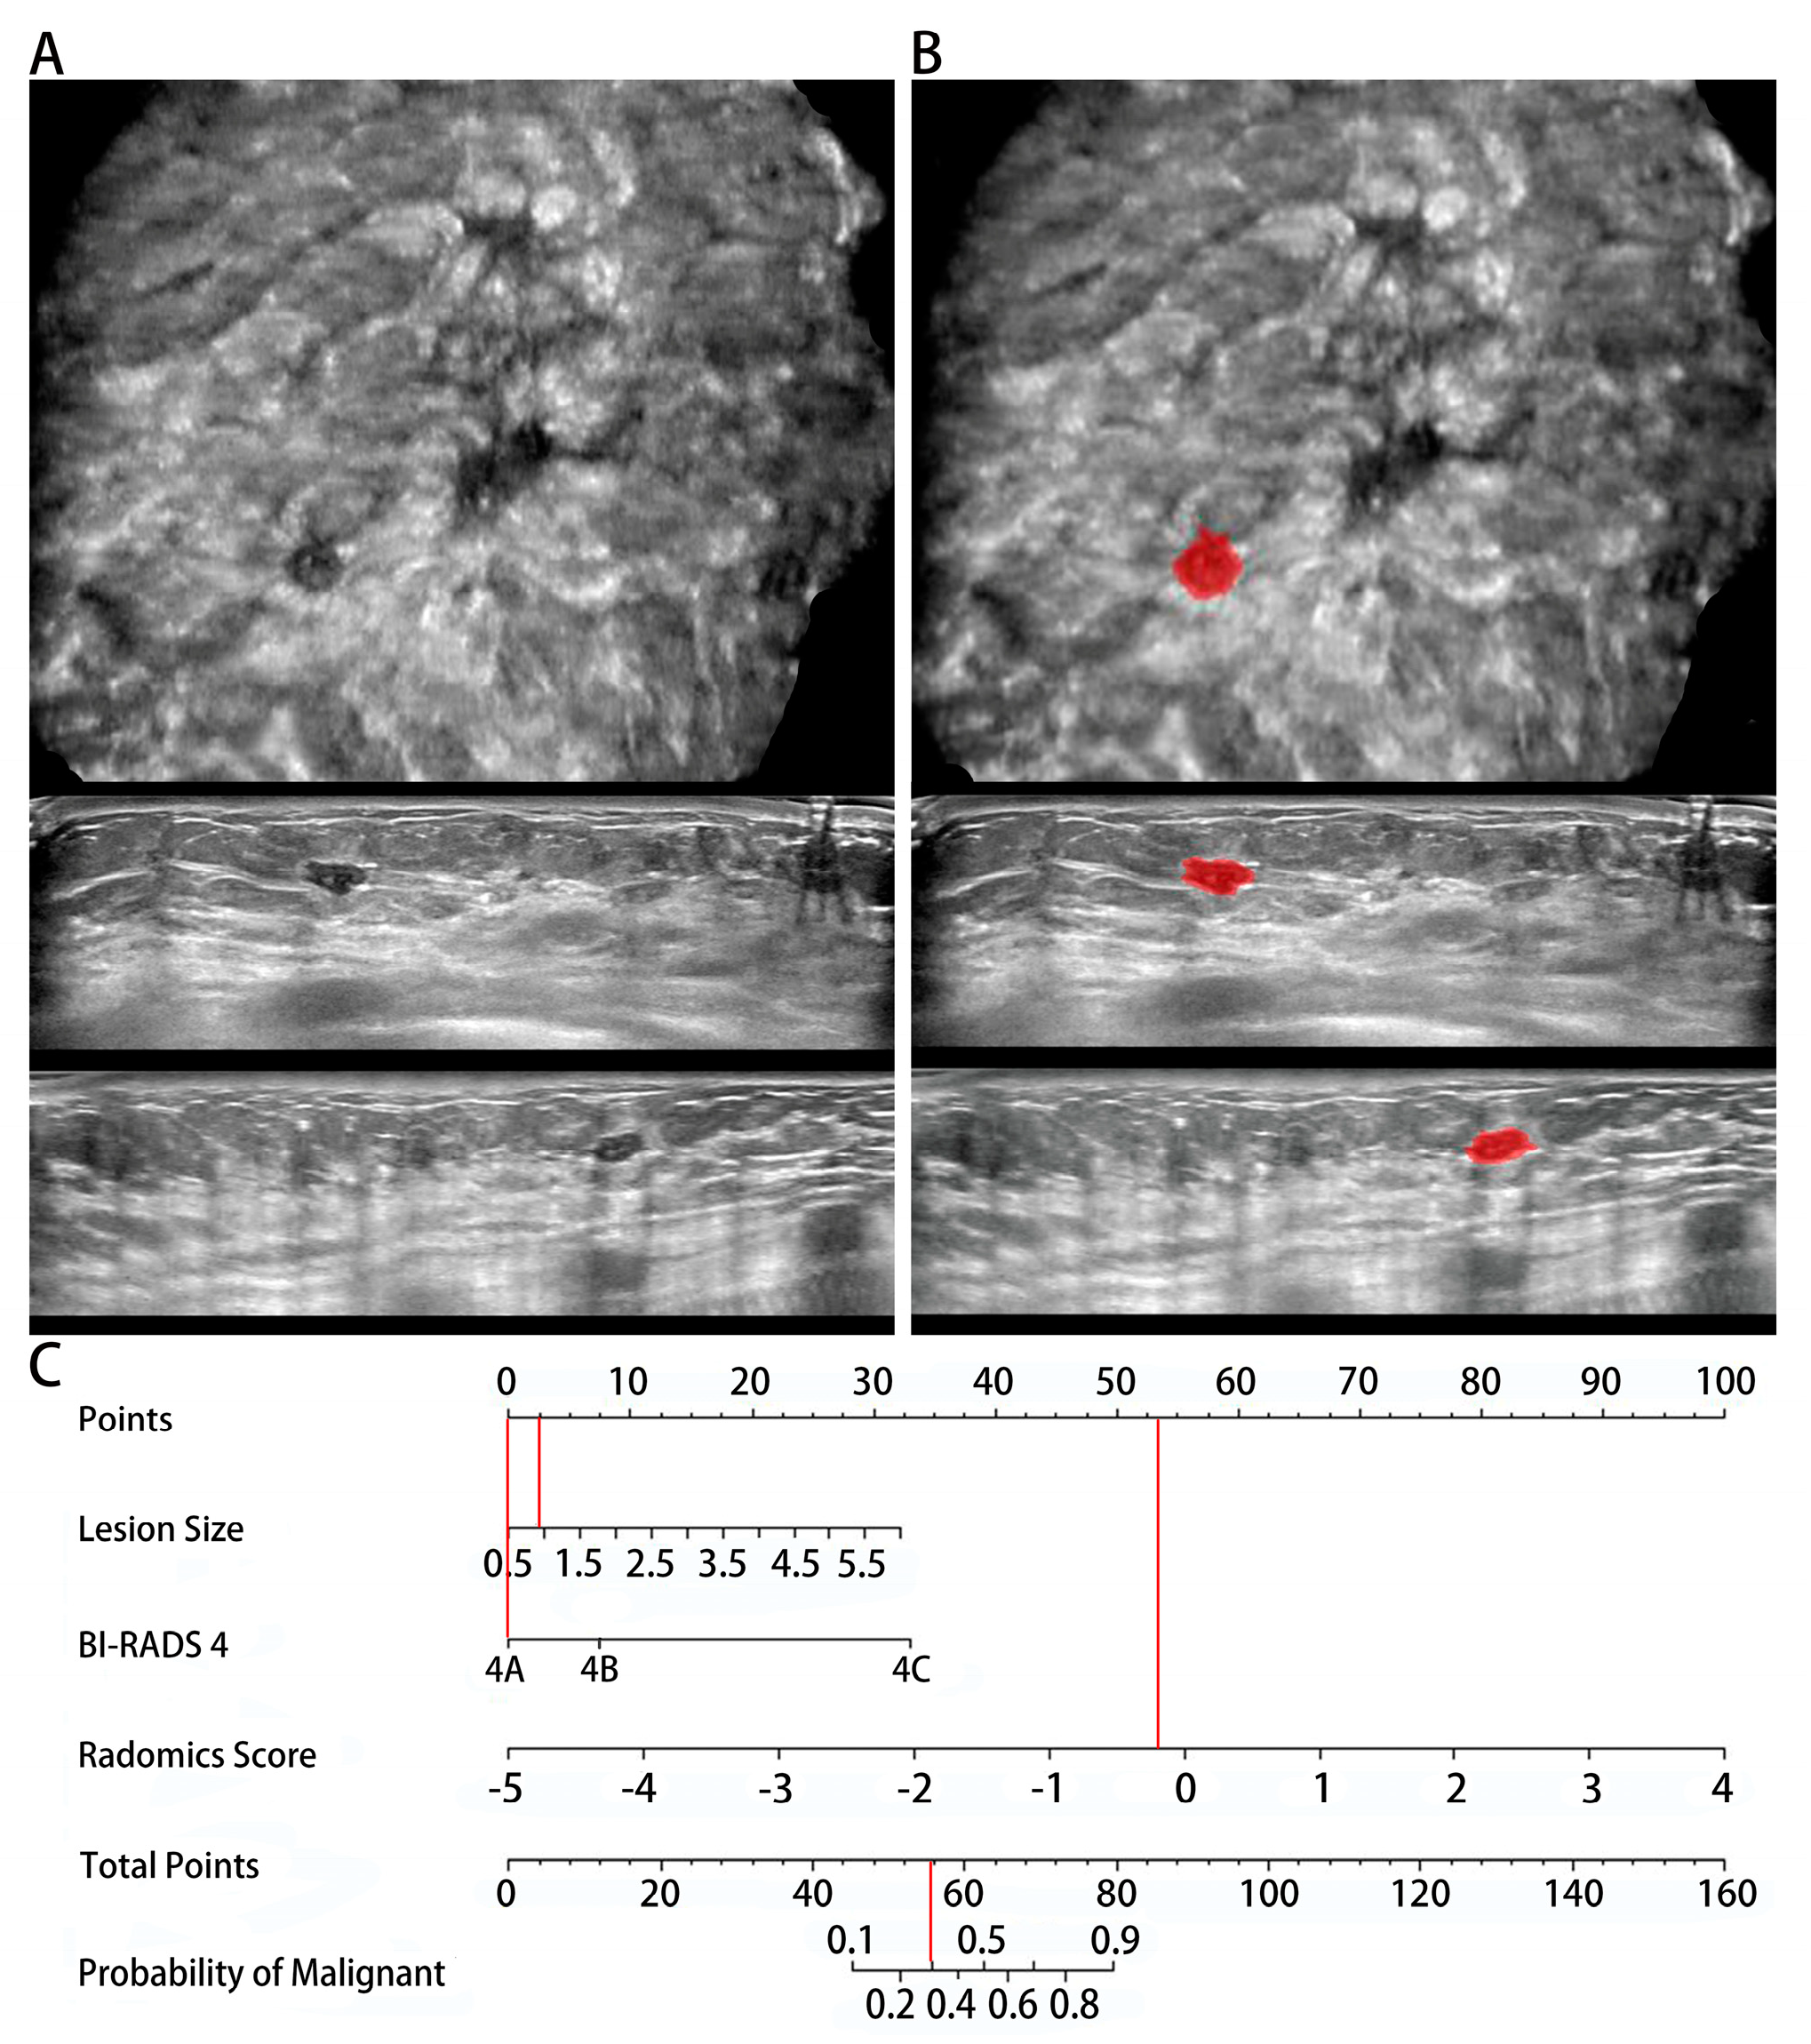

3.3. ABVS Radiomic Nomogram